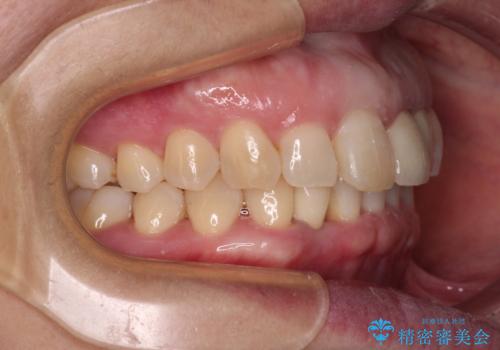

- 下顎前歯が抜けそうとのことで来院された患者様です。

初診の状態ではすぐにでも抜けそうな状態で、インプラントによる補綴治療を行うこととしました。

インプラント治療に際し、前歯の叢生に対する矯正治療を提案したところ、興味を持たれたので、インビザライン・ライトによる矯正治療を行うこととしました。

抜歯後にスペースができると恥ずかしいため、抜歯した歯を接着剤で固定した上で矯正治療を行い、その後インプラントやオールセラミッククラウンの装着を行うこととしました。